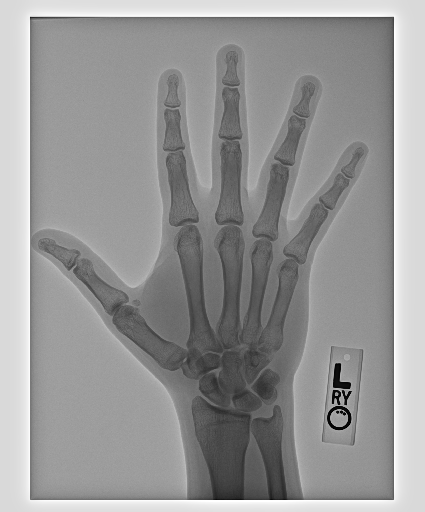

In this work, we focus on a subset of the MURA dataset [17] containing only hand images. In total, we have 5,543 images of 2,018 studies of 1,945 patients. Each study is labeled as negative or positive, where positive means that there was an anomaly diagnosed in this study. There are 521 positive studies, with a total of 1,484 images. Figure 1 shows some examples from the dataset. In summary, our contributions are as follows:

The first step in our pipeline is to detect the X-ray image carrier in the image. To this end, we apply OpenCV’s contour detection using Otsu binarization [14], and retrieve the minimum size bounding box, which does not need to be axis-aligned. This works sufficiently well as long as the majority of the image carrier is within the image (cf. Figure 3). However, the approach might fail for heavily tilted images or those where larger parts of the image carrier reach beyond the image border.

Hand Localization

To further improve the detection of hands, and in particular split the images where two hands are depicted on one image, we manually labeled approximately 150 bounding boxes in the images. Using this small dataset, we fine-tune a pre-trained single shot multibox detector (SSD) [12] with MobileNet as taken from TensorFlow. An exemplary results can be seen in Figure 3.